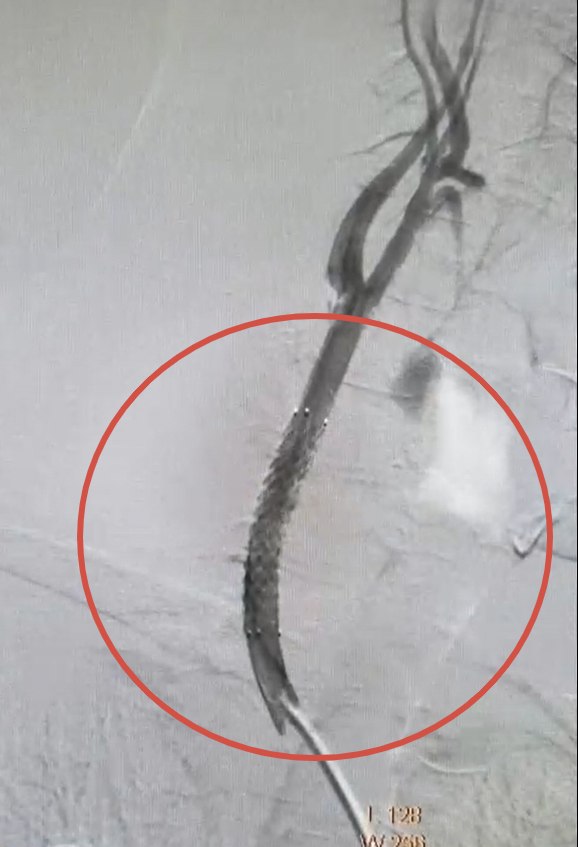

Операцию провели сосудистые хирурги Валерий Казанов и Алексей Подтуркин. Под местным обезболиванием специалисты выполнили небольшой надрез в бедренной артерии, после чего с помощью рентгенологического оборудования направили инструменты к пораженному участку шеи. В артерию установили стент-графт — трубку из полиэстера с металлической опорой, которая укрепила стенку сосуда и предотвратила возможный разрыв. Продолжительность операции составила около часа.

«Мы устранили аневризму изнутри кровяного русла, продвигаясь непосредственно по самим сосудам. Это минимизирует нагрузку на организм больного и ускоряет восстановление», — пояснил главный сосудистый хирург министерства здравоохранения Курской области Леонид Беликов.